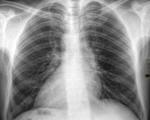

Транспозиция внутренних органов. Это полное или частичное зеркальное отображение органов грудной клетки и брюшной полости. Среди причин патологии - генетические мутации, действие тератогенных факторов на эмбрион. Простые формы транспозиции бессимптомны и выявляются случайно при профилактическом обследовании. Сочетание situs inversus и других внутренних дефектов проявляется нарушениями кровообращения, задержкой роста и развития, частыми инфекционными заболеваниями. Для диагностики назначаются инструментальные методы: УЗИ, рентгенография, МРТ и КТ брюшной полости и грудной клетки. Лечение неосложненных форм аномалии не проводится.

У большинства взрослых пациентов информация о трансплантации органов заносится в медицинские карты, поэтому врач обязан внимательно прочитать документацию. В анамнезе подробно описан вариант инверсии внутренних органов во избежание диагностических ошибок. Если информации об этой аномалии нет, транспозиция выявляется при инструментальных исследованиях - диагностическом ОГК и рентгенографии брюшной полости, УЗИ внутренних органов, КТ и МРТ.